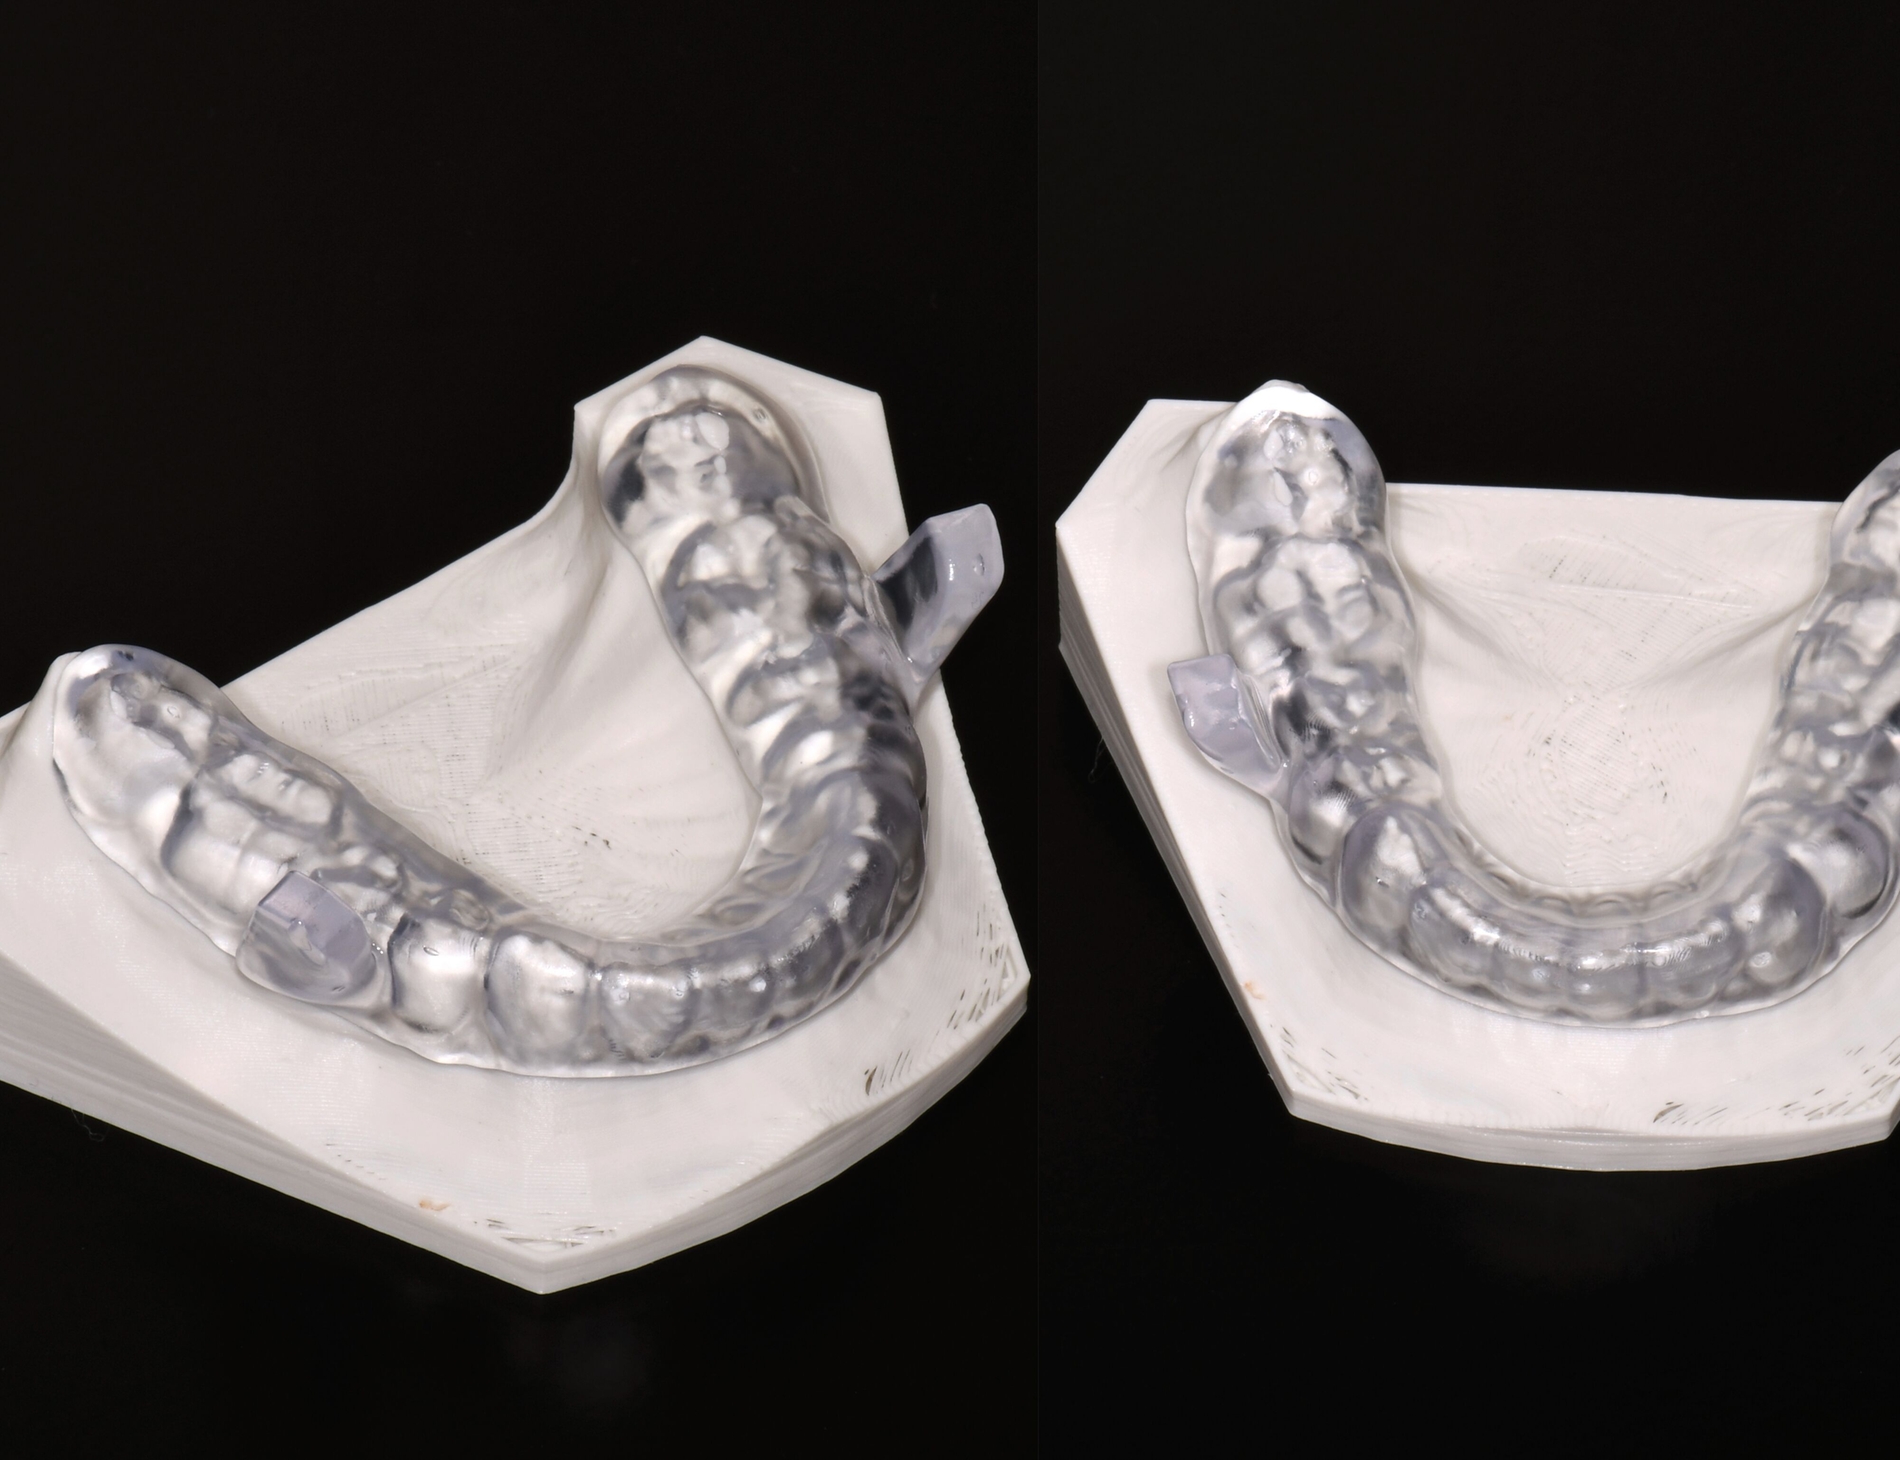

Herausnehmbare Apparaturen

Als hochinnovatives Feld hat sich auch die Herstellung herausnehmbarer Apparaturen im 3-D-Druck entwickelt (Abbildung 4), beschränkt sich jedoch noch auf einzelne Forschungsansätze [Al Mortadi et al., 2012; van der Meer et al., 2016; Graf et al., 2022; Keller et al., 2022]. Intensiv an neuen Konzepten in der Herstellung 3-D-gedruckter herausnehmbarer Apparaturen wird am Universitätsklinikum Heidelberg geforscht. Da herausnehmbare kieferorthopädische Apparaturen im Regelfall bei jungen Patienten eingesetzt werden, kommt dem Vorteil einer unbegrenzten Replikation und einer kostengünstigen und schnelleren Herstellung ein besonderer Stellenwert zu.

Im Unterschied zu konventionellen Apparaturen bestehen die 3-D-gedruckten Apparaturen vollkommen aus Kunststoff. Eine Einarbeitung metallischer Elemente nach dem 3-D-Druck ist möglich [Al Mortadi et al., 2012; Al Mortadi et al., 2024], erfordert jedoch zusätzlichen Zeitaufwand. Zur Herstellung herausnehmbarer Apparaturen eignen sich konventionelle praxisinterne 3-D-Stereolithografie-Drucker, die in vielen Fällen bereits im regulären Praxisalltag zum Modelldruck verwendet werden. Die verwendeten Kunststoffe sollten dabei eine Klasse-IIa-Zertifizierung aufweisen, so dass ein sicherer langfristiger intraoraler Einsatz der Apparatur gewährleistet ist. Weiter muss die Apparatur nach dem 3-D-Druck gemäß den Herstellerangaben nachprozessiert werden. Im Regelfall beinhaltet dieser Prozess ein Waschen in Isopropylalkohol (IPA) sowie eine Nachhärtung im Lichthärtegerät. Eigens durchgeführte Studien sowie die bisherige klinische Erfahrung bestätigen eine hohe mechanische Stabilität, eine hohe Passgenauigkeit sowie eine breite Akzeptanz der Patienten [Roser et al., 2021; Roser et al., 2023; Segnini et al., 2023]. Des Weiteren wecken die 3-D-gedruckten Apparaturen bei den meist jungen Patienten großes Interesse, was wiederum die Trage-Compliance unterstützt. Durch weitere Entwicklungen im 3-D-Druckbereich wird zukünftig auch ein Farbdruck möglich werden.